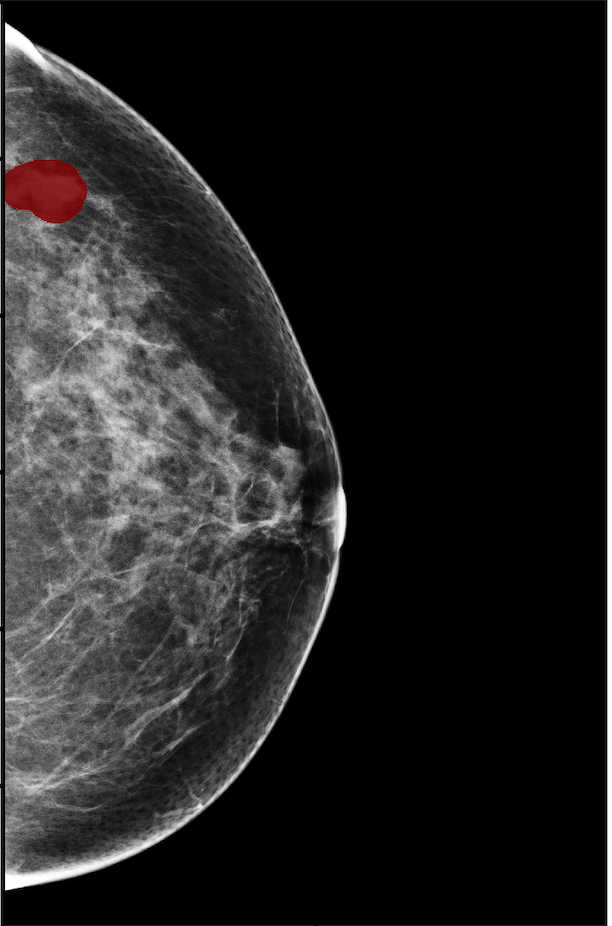

The NYU Breast Cancer Screening Dataset [78] includes 229,426 exams (1,001,093 images) from 141,472 patients.222Our retrospective study was approved by our institutional review board and was compliant with the Health Insurance Portability and Accountability Act. Informed consent was waived. Each exam contains at least four images which correspond to the four standard views used in screening mammography: R-CC (right craniocaudal), L-CC (left craniocaudal), R-MLO (right mediolateral oblique) and L-MLO (left mediolateral oblique). An example is shown in Figure 3.

Across the entire dataset (458,852 breasts), malignant findings were present in 985 breasts () and benign findings in 5,556 breasts (). All findings are confirmed by at least one biopsy performed within 120 days of the screening mammogram. For the remaining screening exams that were not matched with a biopsy, we assigned labels corresponding to the absence of malignant and benign findings in both breasts. In each exam, the two views of the same breast share the same label.

For all exams matched with biopsies, we asked a group of radiologists (provided with the corresponding pathology reports) to retrospectively indicate the location of the biopsied lesions. This way we obtained the segmentation labels: where if pixel belongs to the benign/malignant findings. An example of such a segmentation is shown in Figure 3. In all experiments (except for experiments in Section 3.6 that assess the benefits of utilizing segmentation labels), segmentation labels are only used for evaluation. We found that, according to the radiologists, approximately of exams were mammographically occult, i.e., the lesions that were biopsied were not visible on mammography, even retrospectively, and were identified using other imaging modalities: ultrasound or MRI.